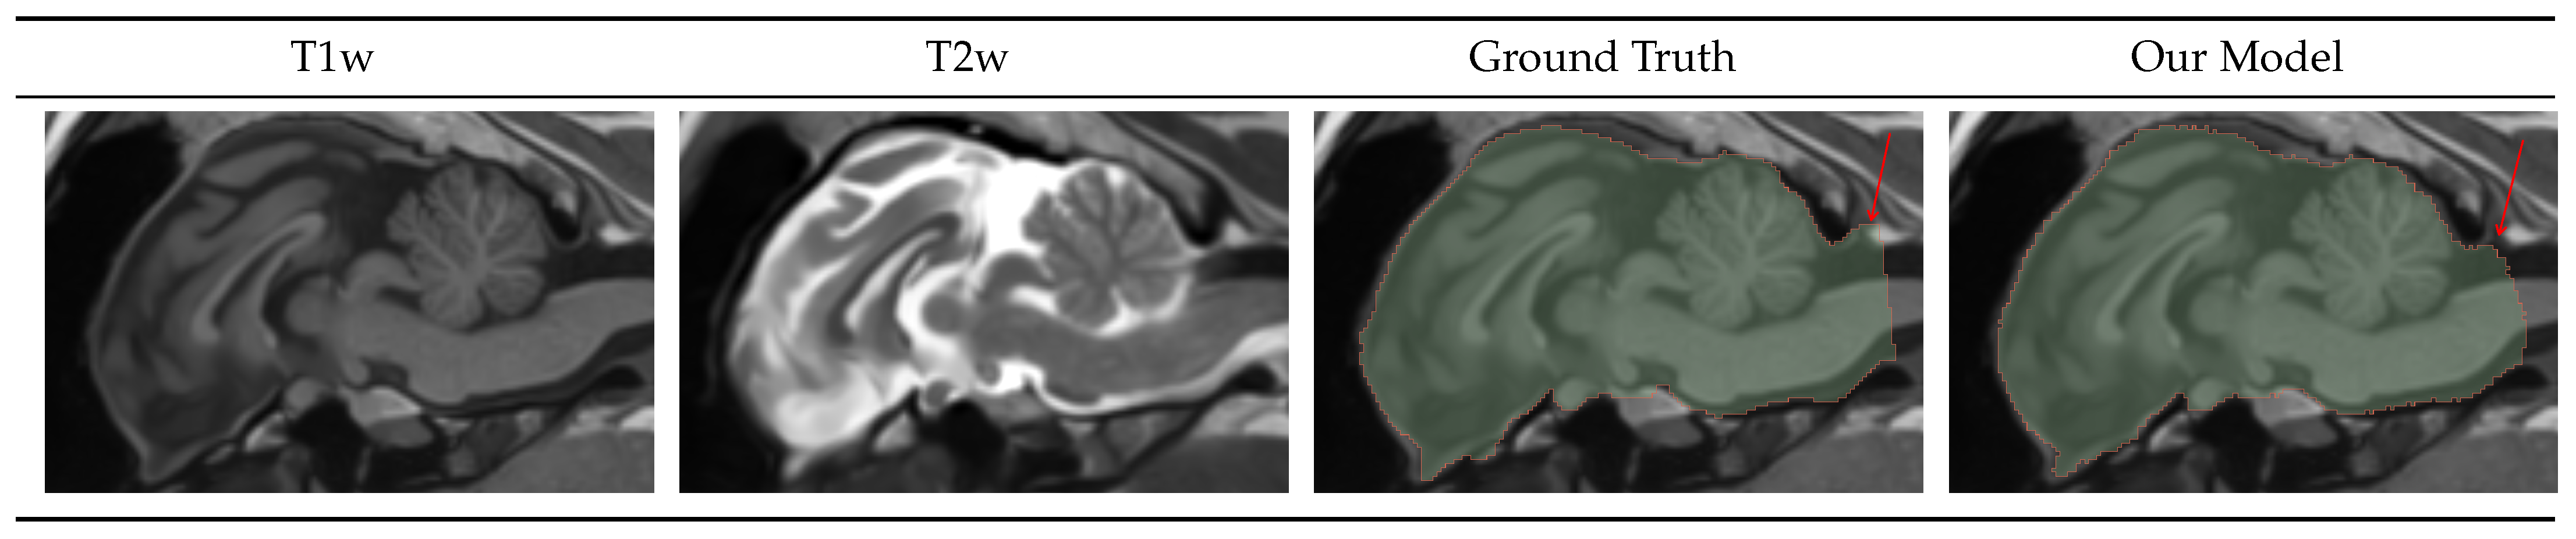

4.1.1. Brainmask

4.1.2. Intracranial Volume Mask